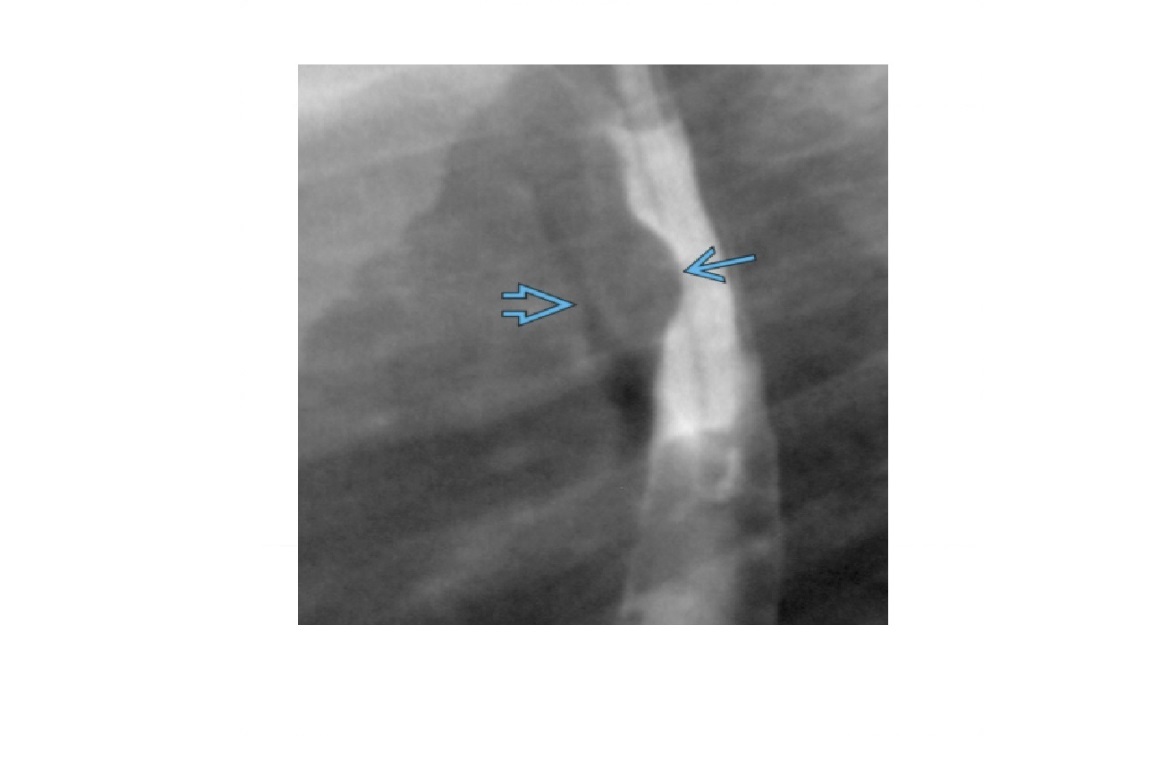

Traction diverticulum

Dysphagia in elderly person. Previous TB.

Barium-filled tented or triangular outpouching in the mid oesophagus

Acquired condition due to subcarinal or perihilar granulomatous lymph node pathology (TB, histo)

External force on oesophageal wall, such as mediastinal inflammation, that adheres and pulls on oesophageal wall